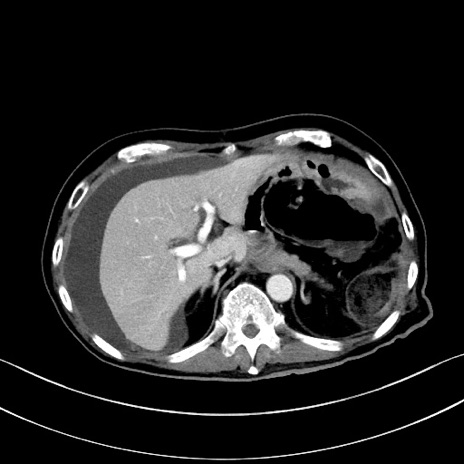

冠状断像

【症例】60歳代男性

【主訴】嘔吐

【現病歴】胃癌にて胃全摘後。食思不振が悪化し、夜中に嘔吐することがある。

【既往歴】胃癌、胃全摘、脾摘、胆摘後

【データ】WBC 5900、CRP 10.56